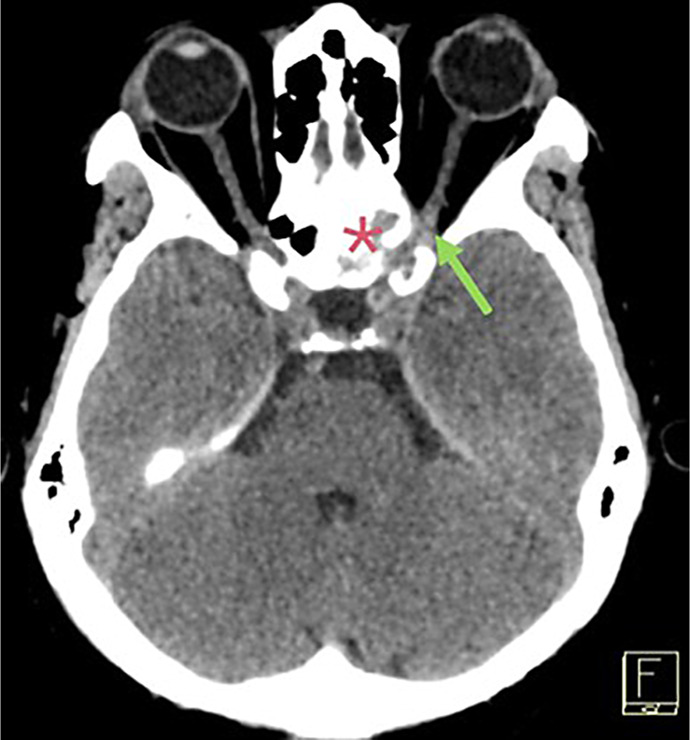

Case report: A 57-year-old woman with a history of infiltrative ductal carcinoma of the breast diagnosed 12 years earlier presented with progressive left-sided vision blurring and headaches for 3 weeks. Imaging revealed a heterogeneous lesion in the left sphenoid sinus compressing the optic nerve. The metastatic breast carcinoma with histopathological and immunohistochemical profiles matching the primary tumour was confirmed by biopsy. Because of the lesion's unresectable nature and additional metastases to the bones and lungs, palliative treatment was initiated, consisting of intensity-modulated radiation therapy and systemic therapy with abemaciclib and letrozole. After treatment, the patient's vision improved, and follow-up imaging showed reduced lesion size.